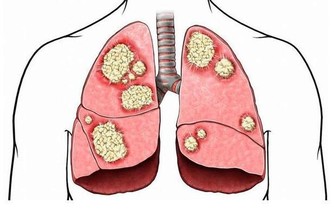

扁桃體結石也會引起口臭

「扁 桃體結石引起的口臭並不少見,大人小孩都可能會出現」,北京中醫醫院耳鼻喉科副主任醫師姜志輝解釋。 扁桃體是人體的免疫器官,位於口咽側壁,包含有 很多隱窩,其中位於扁桃體上極的上隱窩就容易出現結石。 正常情況下扁桃腺隱窩沒有分泌物。 當扁桃體出現急慢性炎症時,就會有脫落上皮、大量淋巴細胞, 白細胞、以及各種致病菌自隱窩排出,若隱窩口堵塞而引起分泌物堆積,時間長了還會導致一些鎂、鈣等無機鹽沉積而引起結石。 這些腐敗的分泌物就會引起口 臭。

不過,這種口臭跟平時的口腔衛生沒有多大關係,刷牙、漱口等都無法達到預防和減輕扁桃體結石引起的口臭。

姜志輝提醒, 扁桃體結石只需要清除乾淨就可以了,一般不需手術。 如果結石不嚴重,在局部麻醉下用專用工具直接把結石摳出來就可以了。 如果經常扁 桃體反復發炎,總是感覺咽部異物感,並伴有口臭的人,最好及時到醫院的耳鼻喉科做專科檢查。 生活中要注意提高自身免疫力,避免局部反覆感染。

另 外,蔡立泰醫師也表示,扁桃腺結石通常看起來像白色或微黃色的小石頭,有時候吐出來時,可以把這些小石頭壓碎,並出現臭臭的味道。扁桃腺結石目前 大多認為是由食物的殘渣及壞菌卡在扁桃腺表面的隱窩中所形成。有些人會感覺到喉嚨卡卡的感覺,嚴重的患者更可能出現頭痛、咽喉疼痛、吞嚥困難、耳朵痛癢、 甚至嘔吐等情形。也因為這些細菌和食物的殘渣以及部分壞死組織的鈣化,所以可能在講話時散發出一些腐爛的臭味,也就是我們所謂的口臭。

造成扁桃腺結石的原因,除了長期發炎導致以外,口腔清潔不夠、喜愛吃刺激食物、油炸物、作息不正常、熬夜等等都是要注意的危險因子。